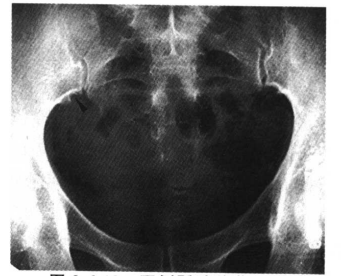

11.坐骨、耻骨软骨联合处不规则愈合,为正常变异,一般为双侧对称,有时仅为一侧,不要误认为骨缺血坏死(图11)。

图11 坐、耻骨联合处不规则愈合,不要误认为坐、耻骨联合处缺血坏死